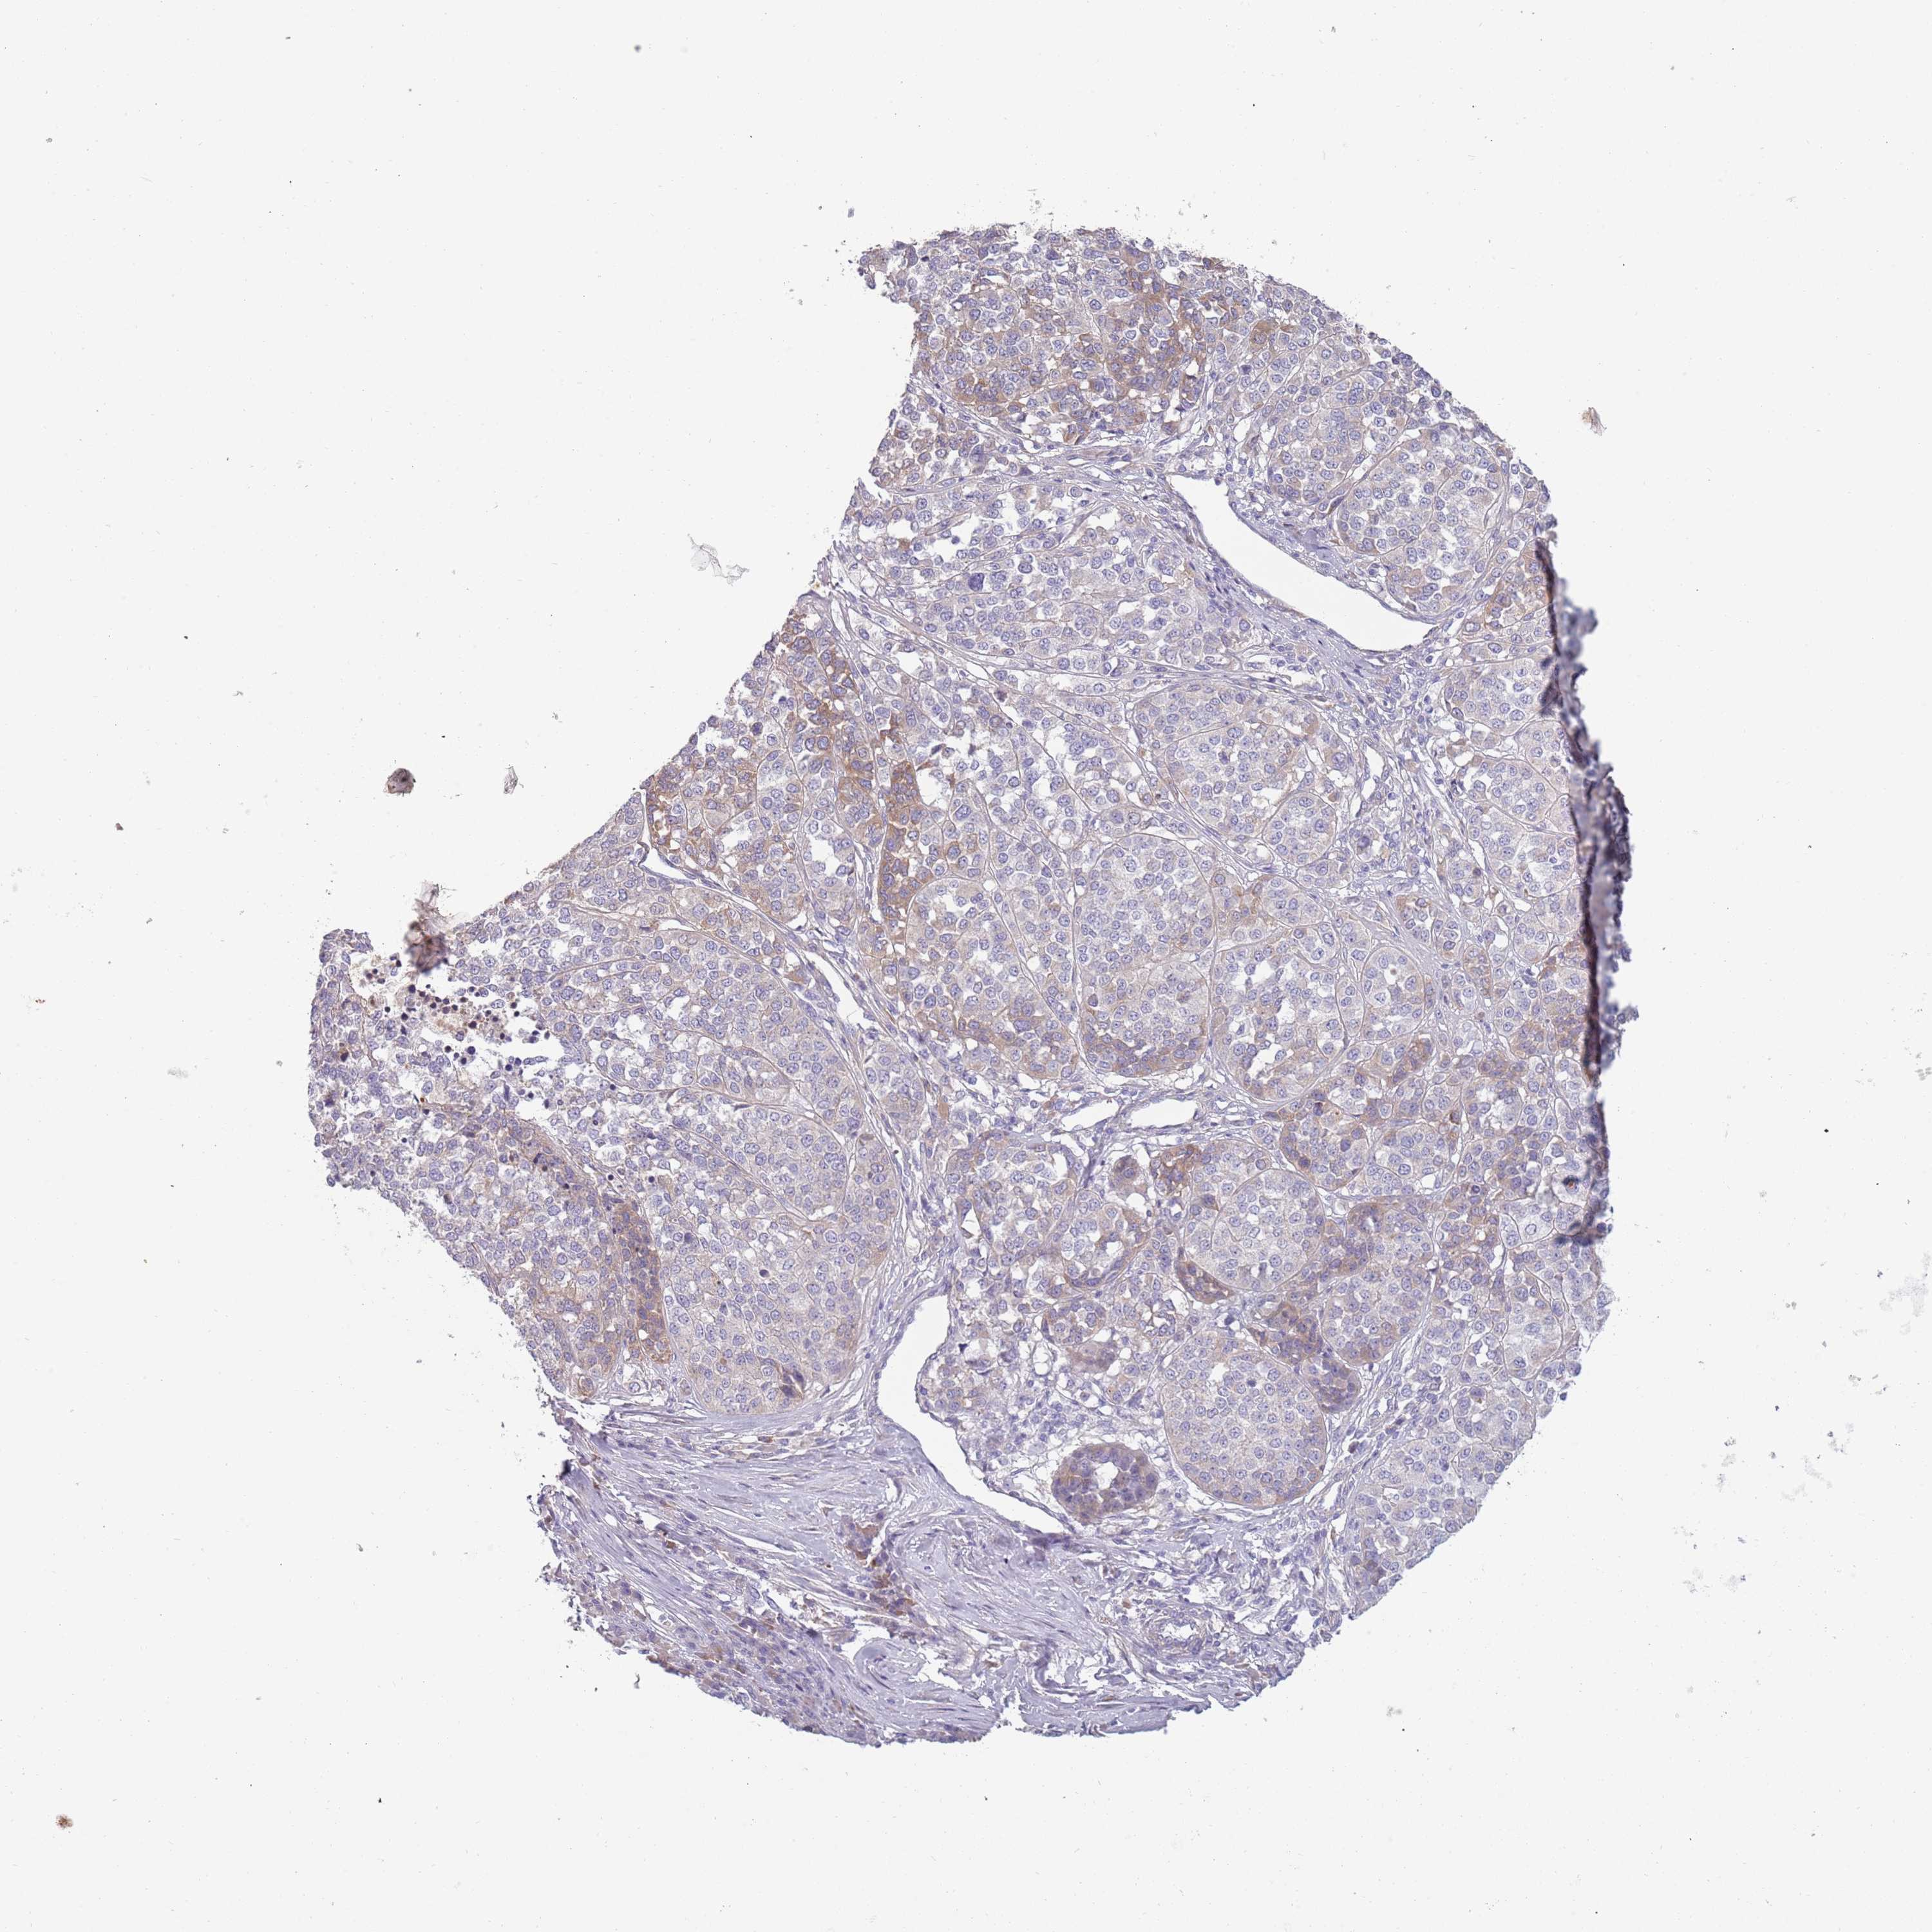

MELANOMA - Protein expressioni

A mouse-over function shows sample information and annotation data. Click on an image to view it in a full screen mode. Samples can be filtered based on level of antibody staining by selecting one or several of the following categories: high, medium, low and not detected. The assay and annotation is described here.

Note that samples used for immunohistochemistry by the Human Protein Atlas do not correspond to samples in the TCGA dataset.

Antibody stainingi

Antibody staining in the annotated cell types in the current human tissue is reported as not detected, low, medium, or high, based on conventional immunohistochemistry profiling in selected tissues. This score is based on the combination of the staining intensity and fraction of stained cells.

Each image is clickable and will lead to virtual microscopy that enables deeper exploration of all samples and also displays staining intensity scores, fraction scores and subcellular localization as well as patient and tissue information for each sample.

Antibody HPA047154

Staining

High

Medium

Low

Not detected

Intensity

Strong

Moderate

Weak

Negative

Quantity

>75%

75%-25%

<25%

None

Location

Nuclear

Cytoplasmic/membranous

Cytoplasmic/membranous,nuclear

Malignant melanoma, NOS

Malignant melanoma, Metastatic site